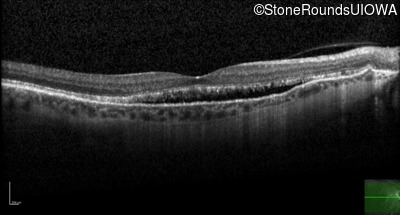

Age at visit: 58 years